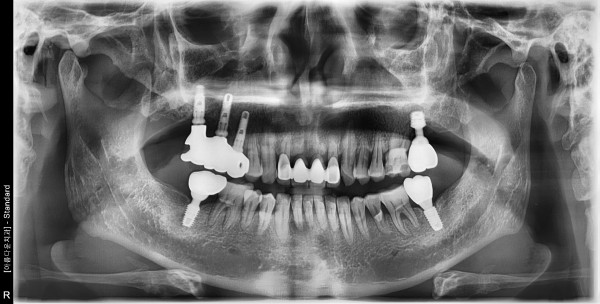

60대 남성 임플란트 식립

2bbed4f5a66a6508b7cf5ac7d6acce9e_1760322